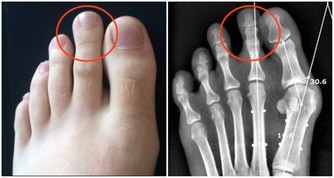

互相夾菜,會傳染胃病?

每次聚餐,菜餚豐盛活色生香,家人朋友頻頻舉箸夾菜,殊不知,一種叫幽門螺桿菌(Hp)的細菌可能在大快朵頤中彼此傳播。

Hp是人與人之間經口—口、胃—口傳播的,Hp感染者的唾液沾到菜餚上,取食者就有被Hp感染的可能。

不要小覷這種寄居於胃黏膜的細菌,它的致病性非同一般,已被確認是引發活動性胃炎、消化性潰瘍及胃癌的罪魁。

建議:聚餐最好使用公筷,杜絕Hp的感染和擴散。